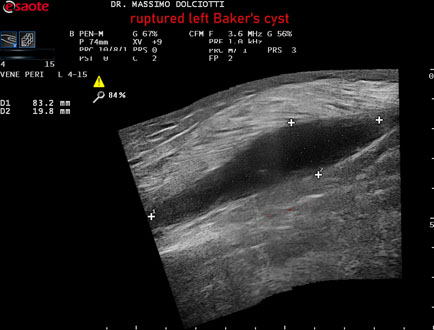

Data inserimento: 02/02/2026

Ecografia del: 27/01/2025

Strumento: Esaote MyLab Eight

Sonda: Lineare Multifrequenza 4-15 MHz

Età Paziente: F 84 anni

Motivazione dell'esame: da 1 mese edema e dolore alla gamba sinistra.

Commento all'esame: le immagini ed il video documentano formazione anecogena al cavo popliteo sinistro, che si estende fino all'inserzione del gemello mediale, delle dimensioni di 83 x 19 mm, da ricondurre a raccolta fluida per rottura di cisti di Baker.

Conclusioni: rottura della cisti di Baker sinistra (ruptured left Baker's cyst).

In collaborazione: Dr.ssa Marica Manfredi - Ancona, Dr. Ilir Qose - Ancona

Presentazione: Dr. Massimo Dolciotti - Ancona